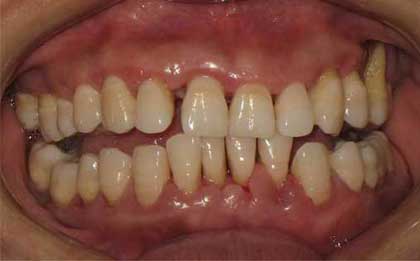

牙周炎是累及四种牙周支持组织(牙龈、牙周膜、牙槽骨和牙骨质)的慢性感染性疾病,往往引发牙周支持组织的炎性破坏。如果不治疗任其发展,终导致牙齿松动脱落。那么重度牙周炎怎么治疗?下文为大家揭晓重度压住炎的治疗方法。

这适用于患牙周病的每位患者。对于出现急性龈脓肿、急性牙周脓肿、急性坏死性龈炎等急症的患者,应根据情况加以处理。拔除无望保留的牙齿,以保持较长时期的牙周健康。进行洁治、刮治、根面平整等以清除龈上、龈下的菌斑,牙石及坏死牙骨质。必要时进行松动牙暂时性固定、调合、药物辅助治疗。这一阶段的任务是消除局部致病因素,加强患者意识。因此对患者进行口腔卫生指导,纠正患者不良生活习惯等十分重要。应使患者了解牙周炎病因及建立良好的口腔卫生习惯的重要性,教会患者清除菌斑的方法,如正确刷牙方法及正确使用牙线、牙签、间隙刷等菌斑清除工具。基础治疗后要对疗效进行再评估。

基础治疗后2-3个月对牙周状况再评估,若某些牙位的探诊深度仍在5mm以上且探诊出血,或根分叉病变I-II度,或牙龈及牙槽骨形态不良,则需要进行手术治疗。牙周手术不但可在直视下进行彻底的根面平整,清除感染组织,还可以纠正不良的牙龈外形、不良牙槽骨形态、根分叉病变,并可进行牙周组织的再生性治疗。